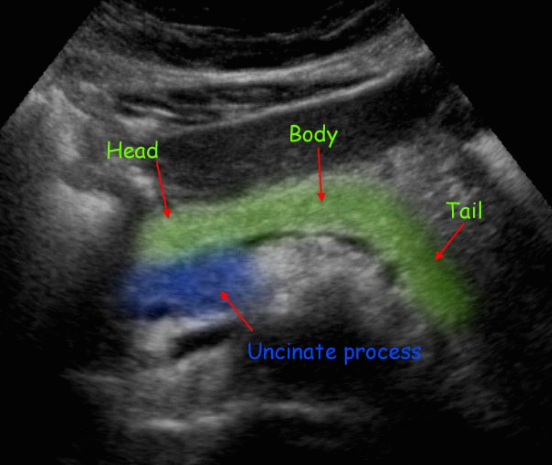

췌장의 해부학 (normal anatomy)

췌장은 복막 후 장기(retroperitoneal organ)로 다양한 효소를 생산하여 음식물을 소화시킨다. 췌장은 췌두부(pancreas head), 췌체부(body), 췌미부(tail)로 구분하며 췌두부에는 구상돌기(uncinate process)가 있다. 태생기에 복측(ventral pancreas)과 배 측(dorsal pancreas)으로 발생하여 췌체부는 전측(anterior)으로 췌두부와 췌미부는 후측으로 휘어져 있다.

췌장의 크기는 길이 약 12cm이고 두께는 췌두부의 약 2.5cm, 체체부 약 2cm, 췌미부 1.5~2cm, 무게는 80g 정도이다.

췌장은 우측에 십이지장, 좌측에 비장, 전측에 위장, 상측에 간, 후측에 대동맥, 대정맥, 상장간막정맥, 상장간막동맥, 비장정맥이 있다.